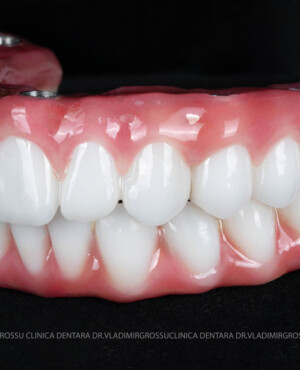

Caz 2

- Posibilitatea realizării unei proteze cu 12-14 dinți, oferind un aspect estetic natural și funcționalitate optimă.

- Proteză definitivă realizată din metaloceramică sau zirconiu, cu 12-14 unități (soluția recomandată).